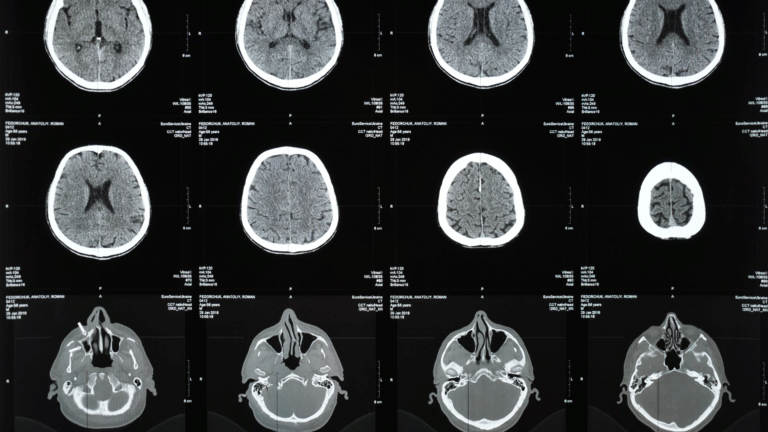

Proving that a collision caused spinal or neck damage requires detailed medical documentation. Baker Matthews Law works closely with orthopedic surgeons, neurologists, and rehabilitation physicians to interpret medical scans, diagnostic imaging, and surgical notes. These experts confirm how the injury occurred and rule out unrelated preexisting conditions.

A personal injury attorney in Austin builds medical evidence by organizing every piece of documentation into a coherent timeline that matches the events of the crash. Baker Matthews Law integrates emergency room reports, MRI findings, and specialist evaluations into a comprehensive presentation that demonstrates both the origin and severity of the injury. This method eliminates doubt about causation and ensures the client’s condition is accurately represented in negotiations or court proceedings.

Herniated and bulging discs occur when the impact of a crash compresses the spinal column and forces the soft inner material of the disc outward. This condition can cause nerve compression, radiating pain, and weakness in the arms or legs. Baker Matthews Law collects MRI scans, orthopedic evaluations, and surgical reports to prove both the presence and severity of these injuries. We also include pain management records and rehabilitation summaries to demonstrate the long-term nature of recovery.

Spinal and neck injuries often progress through several stages of care. The first involves immediate emergency evaluation, followed by diagnostic imaging such as MRI or CT scans to assess damage. Patients may then undergo surgical intervention, physical therapy, and pain management programs to restore function and mobility. Baker Matthews Law ensures that each phase of care is reflected in the legal claim.